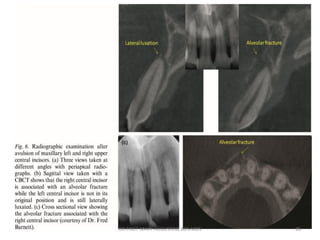

• Radiographic Examination